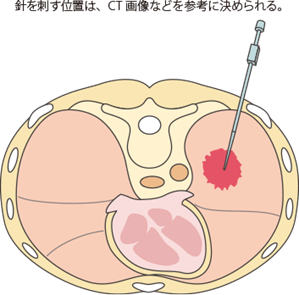

体外から針を刺して細胞をとる:穿刺細胞診

病巣が非常に末梢にあって気管支鏡からのブラシが届きそうになく、体の外側から針で病巣に届く場合、あるいは体の外側に手で触れるリンパ節が腫大しているときなどに行います。

リンパ節の場合はその表面を触れながら、表面の一部を局所麻酔して少し太い針でリンパ節に針を突き刺して吸引します。注射器の中身をスライドグラスに吹き付けて固定します。確実性も安全性も高い検査です。

肺末梢の病変の場合はそのままでは触れることができませんので、X線透視の上で確認しながら行います。これは経皮肺生検の項で詳しく説明します。標本作成方法はリンパ節穿刺と同じです。

皮膚の上から針を刺して細胞をとる:経皮肺生検

皮膚の上から細い針を刺し、肺の中にある病巣から検体を採取します。採取した検体は病理・細胞診にまわして診断をつけます。

近年はCT画像を見ながら(CTガイド下で)行われるようになりました。

病巣のある部位の皮膚を消毒し、皮膚・筋肉・胸膜に局所麻酔をかけてから、太さ約1mmの針を皮膚の上から刺し、病巣まで進めます。針が病巣に到達したら、そのまま注射器で吸引するか、針にセットされたカッターで病巣の一部を切り取ります。これを2〜3回繰り返し、針を刺した部分を消毒し、異常がないかどうかを確認して終了します。 全体で15分ほどの検査です。

経皮肺生検は、いくつかの危険性があります。肺はやわらかいスポンジが詰まった風船のような臓器です。それを針で刺すので穴があいて空気が漏れ、肺がしぼんでしまうことがあります(気胸といいます)。たまに、漏れた空気が皮膚の下に溜まることもあります(皮下気腫といいます)。また、肺にはたくさんの血管が通っているのでその血管に針があたって出血することがあります。その他には、麻酔薬のアレルギー、胸膜を刺したときに反射で起きるショックなどが考えられます。

こうした合併症のうち多いのは気胸で、程度の軽いものも含めると、たいていの場合に起こっていると考えられます。症状は肩のほうに抜ける感じの痛みと呼吸困難です。呼吸困難は気胸の程度によって症状の強さが異なり、症状が強い場合は入院が必要になることもあります。通常は24時間程度で症状は落ち着き、1週間程度で多くの場合は回復しますが、まれにチューブで肺の中に漏れた空気を抜く処置が必要になることもあります。皮下気腫は何もしないでも回復することがほとんどです。

出血は一般に大量になることはなく、数時間の安静で落ち着きますが、心臓の病気で血液を固まりにくくする薬を飲んでいる方の場合は注意が必要です。

経皮肺生検